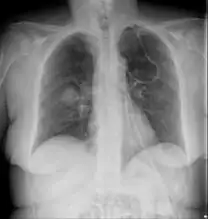

Chest X-ray: likely fungal infection left lung in an immunocompromised person

Imaging

Imaging is often performed, such as CT scan of lungs and sinuses.[38] Signs on chest CT scans, such as nodules, cavities, halo signs, pleural effusion and wedge-shaped shadows, showing invasion of blood vessels may suggest a fungal infection, but does not confirm mucormycosis.[16] A reverse halo sign in a person with a blood cancer and low neutrophil count, is highly suggestive of mucormycosis.[16] CT scan images of mucormycosis can be useful to distinguish mucormycosis of the orbit and cellulitis of the orbit, but imaging may look identical to those of aspergillosis.[16] MRI may also be useful.[39]